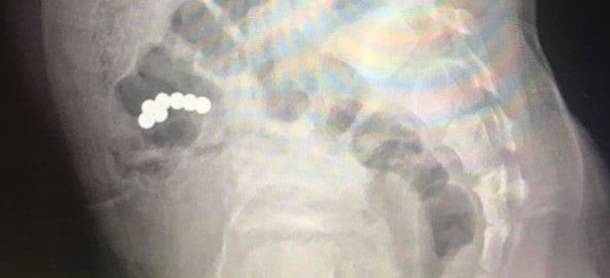

В Ивано-Франковске медики прооперировали пятилетнего мальчика, который проглотил семь магнитных шариков из игрушки.

Во время рентгенологического исследования диагностировали наличие магнитов в кишечнике. Предметы не продвигались в течение 10 дней. Это стало показанием к оперативному хирургическому вмешательству.

Во время операции хирурги обнаружили сращение стенки тонкой кишки, где находились четыре магнита, со стенкой слепой кишки, где были три магнита. Медики удалили лишние предметы.